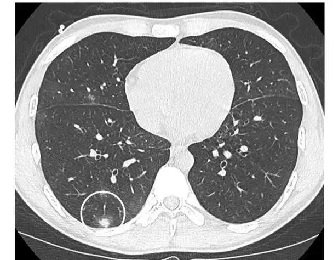

SPN评估关键,薄层CT可清晰展现结节细节,如密度(实性、磨玻璃、混合性)、边缘(光滑、分叶、毛刺)、内部结构(有无空洞、钙化)等特征。如磨玻璃结节伴实性成分、边缘毛刺征、胸膜牵拉等常提示恶性可能;良性结节钙化多呈中心性、层状或爆米花状。增强CT依据结节强化程度辅助判断血供,恶性结节多呈中度至高度强化。

影像学特征分析及随访:如纯磨玻璃结节早期肺癌概率相对低,但随访中若出现密度增加、实性成分增多常提示恶变;分叶征、毛刺征、胸膜凹陷征等在肺癌中多见,而爆米花样钙化多见于错构瘤等良性病变。对于不确定结节,规律的CT复查观察结节大小、形态变化。实性结节增长缓慢,倍增时间常>400天;恶性磨玻璃结节倍增时间约200 - 400天,若短期内迅速增大多为炎性。